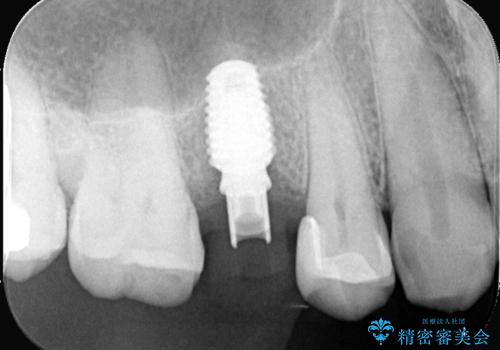

右上5番が根尖性歯周炎と歯周病が同時に併発しており、骨が大きく溶け、歯の動揺も著しかったため保存困難と判断をし抜歯してインプラントで治療を行いました。

インプラントはインプラント周囲炎になりにくいスクリュータイプを使用しています。

従来のインプラント治療では、オペを二回に分けることが主流でしたが今は1回のオペで治療を終える事が出来るようになりました。

インプラントと骨が強度にくっつくように骨密度を上げながらドリリングを行っているのと、患者様の骨の状態に合わせてインプラントの形態を選ぶことで可能となっています。